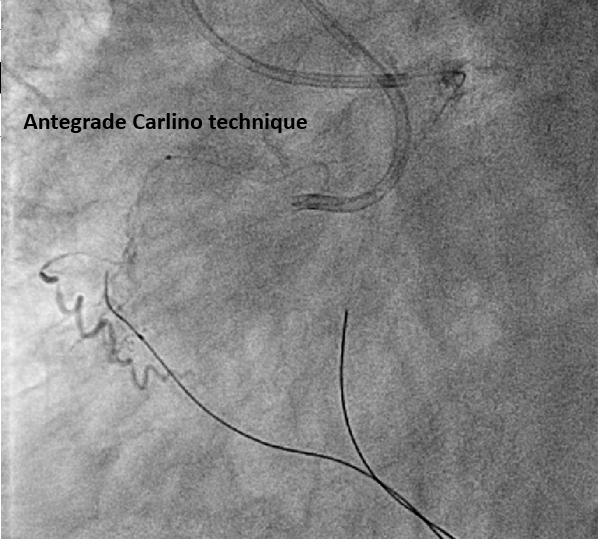

The pLAD ISR was treated first with balloon dilatation followed by DES implantation. An antegrade wire escalation strategy up to Conquest Pro 8-20 for RCA CTO was attempted without success. The wire was left in the subintimal space while a retrograde Sion wire supported by a Finecross microcatheter was advanced through a septal channel to reach the distal CTO cap. The retrograde wire was then exchanged for Gaia 2 and XTA for distal CTO cap penetration. However, a kissing wire technique could not be achieved within the CTO body. Following multiple unsuccessful attempts, the Carlino technique was performed via both the antegrade and retrograde microcatheter. Although a retrograde Fielder FC wire could cross the lesion to the antegrade guiding catheter, this could not be followed by a microcatheter. The retrograde Fielder FC wire was then advanced into the antegrade Tornus microcatheter which also couldn¡¯t cross the lession. Consequently, the retrograde wire was exchanged to RG3. Successful tip-in and externalization with RG3 was achieved afterwards. An antegrade 1.0mm balloon failed to traverse the heavily calcified CTO segment. Therefore, antegrade rotational atherectomy was performed using a 1.25mm burr over the RG3 wire. Following that, the Tornus microcatheter was able to cross the lesion into the distal RCA. A Sion wire was advanced to the distal RCA and the RG3 wire was retrieved. Subsequent balloon dilatation and implantation of two DES were successfully completed

Bi-directional Carlino technique could facilitate intraplaque wire tracking. Usually, after externalisation by RG3 wire, an antegrade microcatheter is advanced distal to the CTO segment for wire exchange, such as a Rotawire in preparation for rotablation. However, in this case, the severe calcification prevented antegrade microcatheter passage. Although the RG3 wire is known to be compatible with rotational atherectomy due to its smaller diameter, its clinical use in this situation is rare. Our case demonstrates the feasibility of performing rotablation over an RG3 wire when neither antegrade nor retroagrde microcatheter passage across the CTO segment is possible.